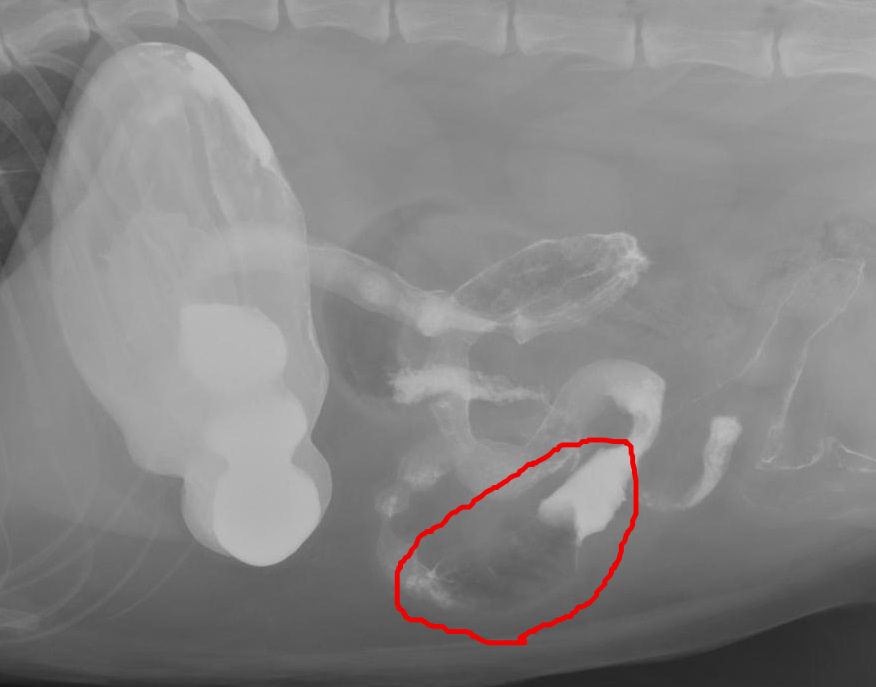

異物① - 神奈川県川崎市麻生区の動物病院 ハルどうぶつ病院 犬・猫の

猫の誤飲 症例報告 動物病院をお探しの方にお役立てになれる最新